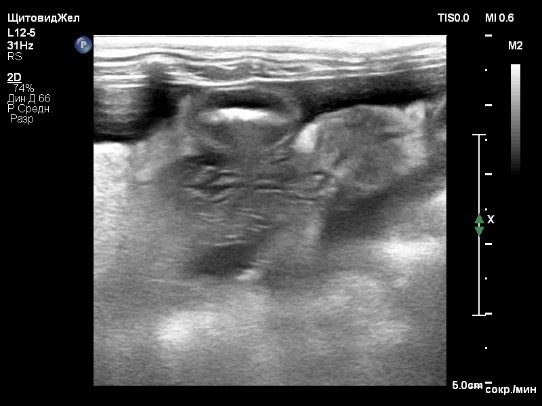

По результатам КТ-ангиографии выявлены следующие изменения (фото 2):

• множественные портокавальные анастомозы, предположительно, приобретенного характера;

• микрогепатия и отек стенки желчного пузыря;

• отек паренхимы поджелудочной железы;

• изменения в стенках желудка и тонкого кишечника, вероятно, обусловленные венозным застоем или воспалительными процессами;

• наличие асцита.

На основании результатов КТ-ангиографии диагноз «врожденный портосистемный шунт» не подтвердился. Были выявлены признаки портальной гипертензии, предположительно, обусловленные первичной патологией печени. Это привело к развитию приобретенных портосистемных шунтов, к отеку паренхимы поджелудочной железы, стенок желчного пузыря и кишечника, а также к асциту вследствие венозного застоя в брюшной полости.